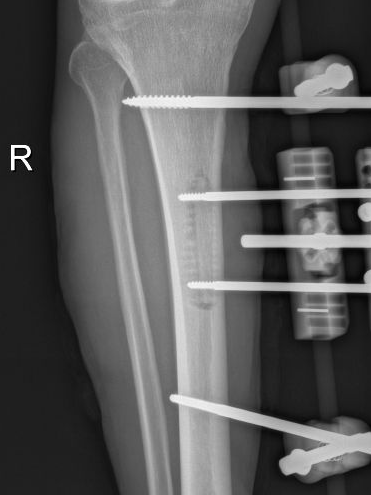

多年来,贵州航天医院各科室紧跟医学前沿,不断强技术、补短板,大力开展新技术、新项目,完成了许多高精尖、高难度、本地区“首例”的技术,填补了医院医疗技术空白,满足了群众日益增长的医疗需求。 贵州航天医院骨科率先在遵义地区开展骨搬移技术,截至目前,已治愈慢性骨髓炎、感染性骨不连、骨缺损、脉管炎、糖尿病足患者200余例,糖尿病足治疗保肢率达到98%。 本期,我们将为大家带来骨科特色技术——骨搬移技术(Ilizarov)。 案例分享 一名59岁的患者,身患糖尿病12年,在来我院3个月前出现了右脚溃烂的症状,来院就诊时,患者的右脚十分红肿,右脚脚趾坏死,伤口处不断流出黑红色脓液,情况十分严重。在接诊到患者时,骨科专家团队高度重视,立刻为患者完善了CT血管造影(CTA)等相关检查,诊断为:2型糖尿病,糖尿病周围血管病变,右糖尿病足。 术 前 考虑到患者情况比较严重,为最大限度保证患者肢体完整,科室专家团队进行了严格的讨论评估,为患者制定了骨搬移技术治疗方案,在征得患者及其家属的同意后,成功通过搬移骨块为患者进行治疗,促进患者病变肢体血管再生。 胫骨横向骨搬移外架固定 清除感染病灶 术后调节外架,通过搬移骨块 促进患肢血管再生 患者在术后三周前来换药,观察到感染得到进一步控制;术后六周复查,患者病变处已愈合,进行CT血管造影(CTA)后可明显观察到足部血管再生。 术后3周 术后6周愈合 CT血管造影见足部血管再生 糖尿病患者全身与局部的问题互为影响,形成恶性循环,糖尿病足溃疡创面迁延不愈,常见干性坏疽、湿性坏疽、趾坏死、深且大的溃疡以及骨髓炎等症状,还可导致脓毒血症,以往为保全生命,患者被迫选择一次或多次截肢。骨搬移技术的发展进步,能在血糖有效控制、局部有效清创下,有效促进患肢微血管再生,改善患肢血供,达到糖尿病足更快治疗康复的目的,并能根据病变情况最大限度的保障患者肢体完整。 什么是骨搬移技术 骨搬移技术是通过使用专用的骨外固定器固定骨段,每天缓慢牵拉,在牵拉搬移过程中,骨段尾部形成新骨及新的软组织,从而修复骨骼缺损及软组织缺损。是治疗大段骨缺损、骨不连、骨感染、肢体畸形的金标准方法,也用于治疗脉管炎、糖尿病足等肢体缺血性疾病。 骨感染缺损 切除感染段 搬移骨段 新骨形成 骨感染根治愈合 骨搬移技术原理 生物组织在持续、稳定、缓慢牵拉下,能刺激细胞分裂、组织再生,骨外固定技术运用该原理,通过持续缓慢调节外固定器形成牵拉张力,促进牵引成骨与相邻组织再生,如神经、血管、肌肉、皮肤等再生,达到治疗大段骨缺损、肢体缺血如糖尿病足等疾病的目的。 骨搬移技术优势 (一)除治疗骨缺损、骨不连外,有更广的适用范围,利用组织再生、血管再生等特性,能大量运用于肢体畸形的矫形、糖尿病足等的治疗。 (二)治疗效果确切,重建肢体外型和功能,极大降低截肢率和残疾率。 (三)明显提高了患者生活质量,极大减轻其家庭及社会负担。 肢体畸形的矫形 慢性骨髓炎 骨段切除 术后1年 濒临截肢的脉管炎术后6周 难愈创面术后3周 贵州航天医院骨科 专家团队 赵学平 骨科主任 主任医师 临床擅长:从事骨科临床工作30余年,对骨科常见疾病的诊治具有丰富的临床经验。 世界中医药联合会脊柱康复专业委员会常务理事,中华中医药学会整脊分会常务委员,中国中西医结合学会骨伤科分会肢体矫形功能重建与康复专家委员会常务委员,中国研究性医院学会骨科创新与转换专业委员会关节外科学组保髋工作委员会常委,中国康复技术转化及发展促进会骨外科与康复技术转化专业委员会常务委员,泛珠三角区域运动医学联盟(PPRD-SMA)理事会常务理事,中国研究型医院学会运动医学专业委员会委员,贵州省中医药学会整脊分会副主任委员,贵州省中西医结合学会银质针专业委员会副主任委员,贵州省康复医学会骨与关节专业委员会常务委员,贵州省人民医院骨科专科联盟常务理事,贵州省康复医学会骨内科专业委员会常务委员,中华医学会贵州省骨科学会委员,贵州省康复医学会脊柱脊髓专业委员会常务委员,贵州省运动医学分会委员,贵州省康复医学会骨与软组织肿瘤专业委员会委员,遵义市医学会创伤分会副主任委员,贵州省康复医学会骨内科专业委员会遵义地区分会常务委员,遵义市医疗事故鉴定、伤残鉴定、工伤鉴定、司法鉴定专家。 长期从事骨科临床研究及教学工作,在国家级、省部级杂志发表论文20余篇,SCI论文2篇,参与主编骨科专著2部,主持省部级科研项目2项,参与指导省部级、市级科研项目6项。 陈明勇 骨科副主任 副主任医师 临床擅长:从事创伤骨科工作约20年,对骨缺损、骨不连、骨肿瘤、肢体畸形等的肢体矫形重建及功能重建,慢性化脓性骨髓炎的根治治疗、糖尿病足的保肢治疗、快速康复理念(ERAS)下的老年骨折的诊治,四肢复杂骨折的诊治,四肢骨折等微创手术治疗具有丰富的临床经验。 2004年毕业于遵义医学院临床专业,曾在中国人民解放军总医院、广西医科大学第一附属医院、上海第六人民医院骨科进修。中国中西医结合学会骨伤科专业委员会横向骨搬移治疗糖尿病足及微血管网再生学组首届委员,遵义市医学会创伤分会常务委员。 瞿 辉 骨科 副主任医师 临床擅长:对骨科的常见病、关节外科、脊柱外科及运动医学疾病的诊治具有丰富的临床经验,熟练掌握骨科手术操作技术。 毕业于遵义医学院临床医学系,2005年前往广州中山大学第一附院骨显微医学部进修学习,2011年前往成都华西医院进修学习,并多次在省内外学习骨科相关知识,是中华医学会骨科分会会员。 赵兴东 骨科 主任医师 临床擅长:擅长骨科的常见病及各种创伤、四肢骨折创伤修复、骨感染、手足疾病的诊治和手足体表畸形的矫形整复,熟练掌握骨科四肢骨病及创伤的手术操作技术,尤其在四肢关节复杂性损伤、手足外伤、组织缺损创面、难治创面的皮瓣修复方面及平足、高弓足矫形方面及四肢慢性疼痛诊治、康复方面具有丰富的临床经验。 硕士研究生,毕业于遵义医学院临床外科系,2015年前往山东省立医院手足外科进修学习;遵义市医学分会创伤分会第一、二届委员,遵义市手外科医学会第二委届员会常务委员;在省级及省级以上期刊发表文章9篇,参编著作2部,参与主持并完成市级课题1项,参与市级课题2项、省级课题1项。 张俊凯 骨科 副主任医师 临床擅长:从事骨科临床工作28年,对创伤骨折、骨感染、骨缺损、骨不连等外科诊治,四肢骨折的微创手术治疗,四肢复杂骨折(如关节内粉碎性骨折、多发骨折等)的损伤控制及手术治疗等具有丰富的临床经验。 1995年毕业于遵义医学院临床专业,2009年前往复旦大学附属医院骨科进修1年。 卢懿明 骨科 副主任医师 临床擅长:从事骨科工作18年,对创伤骨折、四肢骨折的微创手术治疗、四肢复杂骨折(如关节内粉碎性骨折、多发骨折等)的损伤控制及手术治疗,尤其是髋部骨折的PFNA等微创技术,踝关节骨折、膝关节周围骨折的Mipo微创技术等具有丰富的临床经验,开展了4项新技术,发明6项新型专利技术。 2005年毕业于遵义医学院临床专业,2017年,前往南方医科大学第三附属医院骨科进修半年,回院后运用Mipo技术对骨干骨折及干骺端骨折的治疗技术,同时积极开展骨盆骨折、髋臼骨折腹直肌外侧切口的应用;发表了多篇专业论文,经常参与省内外学术交流会授课,获得医院荣誉称号多个。 邬夏荣 骨科 副主任医师 临床擅长:从事骨科工作16年,对四肢复杂骨折、骨肿瘤的诊治,尤其是足踝创伤、慢性踝关节损伤、平足症等诊疗具有丰富的临床经验。 2006年毕业于遵义医科大学临床医学专业,曾在陆军军医大学西南医院进修学习,发表多篇骨科学术论文。 余德怀 骨科 副主任医师 临床擅长:从事骨科工作10余年,对运动医学、骨关节、脊柱外科常见病、多发病的诊治具有丰富的临床经验。 硕士研究生,2011年毕业于遵义医学院临床医学专业,曾前往遵义医科大学附属医院运动医学专业进修学习;是贵州省医学会运动医学分会青年委员,西部关节镜联盟委员;发表多篇骨科学术论文。 冯 乾 骨科 副主任医师 临床擅长:从事骨科工作近20年,熟练掌握骨科多发病及常见病的诊治,尤其对脊柱退变性疾病的诊断及治疗具有丰富的临床经验,主要研究脊柱微创相关治疗方式,能熟练开展椎间孔镜及VBE。 曾前往北京大学第三医院进修学习疼痛及椎间孔镜、首都医科大学友谊医院专业进修脊柱内镜;是贵州省康复医学会第三届脊柱脊髓专业委员会委员;发明专利3项、发表脊柱外科专业论文多篇。 张艳金 骨科 副主任医师 临床擅长:从事骨外科工作16年,对复合伤、多发伤的救治、四肢骨干骨折、关节周围骨折、骨肿瘤、骨髓炎等诊治具有丰富的临床经验。 中共党员,硕士研究生,2006年本科毕业于山西医科大学第二临床医学院,2011年研究生毕业于北京军区总医院;在“老年COPD患者合并髋部骨折的诊治”国际合作课题组研究两年,在老年髋部骨折的诊治方面具有丰富的经验,并发表论文6篇;承担遵义市级课题1项;承担遵义医科大学的临床教学工作,获得遵义医科大学优秀带教老师荣誉。编撰有《骨科疾病诊疗精粹》一书,开展2项新技术,编撰地方规范《务川自治县创伤骨科常见疾病诊疗规范》一书。 赵小锋 骨科 副主任医师 临床擅长:从事骨科临床工作11年,对骨科常见病、多发病诊疗有较为丰富的临床经验,擅长脊柱相关疾病诊断及治疗,尤其是颈、腰、腿疼痛疾病诊断及治疗,擅长胸腰椎骨折微创经皮穿刺内固定术、经皮穿刺椎体成形术、经皮穿刺脊柱内镜下腰椎间盘摘除术、单纯开创腰椎间盘摘除术、腰椎滑脱复位椎间植骨椎融合内固定术、腰椎管狭窄减压融合内固定术及人工髋、膝关节置换术等。 2012年毕业于遵义医学院外科学专业硕士研究生,2019年参加“遵义市115医学人才精英计划”于上海交通大学第一附属医院培训学习,2023年于北京大学第三人民医院脊柱外科进修学习,曾获得遵义市优秀医师荣誉称号。 遵义市手外科第一届委员,遵义市医学会创伤分会第一届委员,遵义市医学会创伤分会第二届委员,贵州省康复医学会第三届脊柱脊髓专业会委员,遵义市医学会烧伤与整形外科学分会委员,发表论文5篇,其中国家级核心期刊1篇,SCI论文1篇,主持市级课题1项并结题,参与市级课题2项。 贵州航天医院骨科简介 基本情况 贵州航天医院(原3417医院)骨科组建于1968年,前身是以创伤和断肢(断指)再植闻名于世的上海市第六人民医院骨科,中国断肢(断指)再植的奠基者、中科院院士陈仲伟等著名专家、学者多次莅临科室指导医疗、教,是贵州省最早拥有专业骨科技术科室之一,在70年代开展了贵州省首例断肢(断指)再植手术。组建50余年来,诊治患者已逾百万,挽救了无数的伤病员,成为了保障遵义地区人民群众健康的重要支撑。 经过几代人的不懈努力,今天的骨科,已由创伤骨科发展至骨病、骨肿瘤、骨结核等领域,现有脊柱外科、关节外科、四肢创伤、手足外科四个亚专科,成为了集医疗、教学、科研于一体的综合学科,是贵州省临床重点专科、遵义市临床重点专科、遵义市骨科临床医学中心、遵义市基层骨科专科联盟理事长单位。 科室目前开放床位110张,共有医护人员50余人,副高级以上专家18人,硕士研究生15人。拥有一流骨科医疗设备多台,每年不定期选派优秀技术骨干到全国各大知名医学院校进修、学习、参观、交流,并邀请国内、国外知名专家教授来院进行交流、指导,通过不断引进国内外先进的诊疗技术,科室医疗技术水平稳步提升,为广大人民群众提供了优质的医疗服务。 专科特色 骨一科 (一)骨缺损、骨不连的肢体与功能重建 胫骨横向骨搬移技术治疗糖尿病足: (二)慢性骨髓炎的根治治疗 (三)肢体缺血性疾病如糖尿病足、脉管炎的保肢治疗 (四)皮瓣修复 (五)复杂创伤的治疗 (六)老年髋部骨折及小儿骨折快速手术 老年髋部骨折: 骨二科 (一)胸腰椎骨折微创经皮椎弓根螺钉固定术 (二)老年性骨质疏松性患者腰椎滑脱脊柱内固定术(骨水泥螺钉) (三)V形双通道脊柱内镜技术(VBE)腰椎融合术治疗腰椎退行性疾病 (四)老年性骨质疏松性骨折(PVP/PKP)术 (五)人工髋关节置换术 (六)双侧股骨头坏死人工全髋关节置换 (七)右侧全髋置换术后假体周围骨折翻修 (八)人工膝关节置换术 (九)人工膝关节假体松动翻修 (十)关节镜技术 传统手术切口 关节镜技术切口 诊疗范围 骨一科 1.四肢创伤、矫形。 2.手、足踝外科。 骨二科